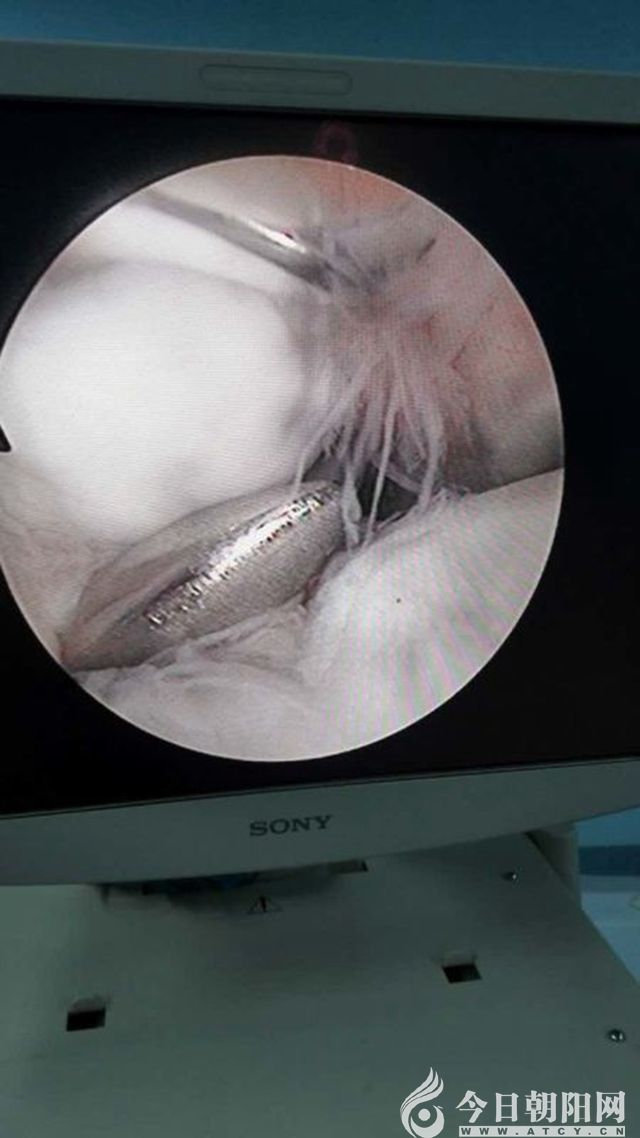

近日,朝陽(yáng)市第二醫(yī)院骨外科(一)病房成功實(shí)施一例肘關(guān)節(jié)鏡手術(shù),為患者取出了肘關(guān)節(jié)內(nèi)的游離體,解除了患者的病痛。目前,患者肘關(guān)節(jié)功能恢復(fù)良好,已痊愈出院。據(jù)悉,此例手術(shù)在朝陽(yáng)地區(qū)尚屬首例。

患者男性,18歲,10年前出現(xiàn)右肘關(guān)節(jié)疼痛,并逐漸出現(xiàn)右肘關(guān)節(jié)活動(dòng)受限、卡阻現(xiàn)象,患者為此苦不堪言。在輾轉(zhuǎn)多家醫(yī)院后,慕名來(lái)到市二院骨外科就診,骨外科(一)病房副主任、主任醫(yī)師徐剛結(jié)合其病史,完善相關(guān)檢查后,診斷為右肘關(guān)節(jié)骨性關(guān)節(jié)炎,右肘關(guān)節(jié)游離體。決定采用關(guān)節(jié)外科領(lǐng)域的新技術(shù)——肘關(guān)節(jié)鏡微創(chuàng)技術(shù)對(duì)該患者實(shí)行手術(shù)治療。經(jīng)過(guò)細(xì)致周密的術(shù)前準(zhǔn)備,為患者成功實(shí)施了肘關(guān)節(jié)鏡微創(chuàng)手術(shù),手術(shù)歷時(shí)50分鐘,切口只有5mm左右,于肘關(guān)節(jié)內(nèi)順利取出一枚1.0*1.5cm大小的游離體。術(shù)后,患者肘關(guān)節(jié)疼痛及卡阻現(xiàn)象消失,屈伸活動(dòng)良好,目前已痊愈出院。